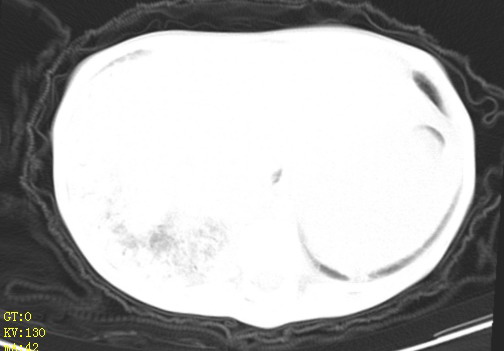

女,12岁,气促、咳嗽2天,3个月前查胸片示:两肺感染,急诊入院查ct,血常规等未检查。

双肺中下野不规则片絮状阴影,中外带明显,双侧胸腔少量积液,心影增大,心腔密度减低,隆突下及左侧气管旁见钙化淋巴结影,考虑双肺感染、心衰;建议结合临床除外h1n1并急性心衰,先心不能排除。

两肺多发片絮状模糊影,以下肺外带居多,内见支气管气像,纵膈窗未减影,两侧胸腔积液,心影增大,结合心超,支持重症肺炎,非常时期,甲型h1n1流感不排除。